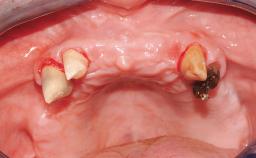

Conventional Loading of Six Implants in the Mandible and Final Restoration with a Full-Arch Metal-Ceramic FDP

A 68-year-old, completely edentulous male patient presented for evaluation and treatment options. He reported excellent general health and was taking no regular medication. He had been edentulous for approximately 12 years, having lost his teeth to periodontal disease and dental caries. The patient’s chief complaint was incompetent function. His secondary concerns included his appearance and the desire for a predictable outcome. He attributed his reduced functional capacity to his lower complete denture, which he described as poor. He was particularly concerned with the denture’s instability and poor fit. In general terms, he was satisfied with the maxillary complete prosthesis. The maxillary prosthesis was characterized by adequate retention, stability, and support, although the fit was considered less than ideal.

Case Type Edentulous Mandible

Jaw Mandible

Area Full-Arch

Defining Characteristics Fully edentulous lower jaw to be rehabilitated with two or more implants